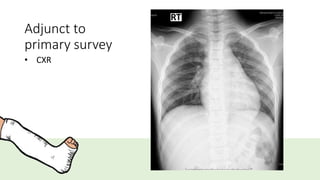

Adjunct to

primary survey

• CXR